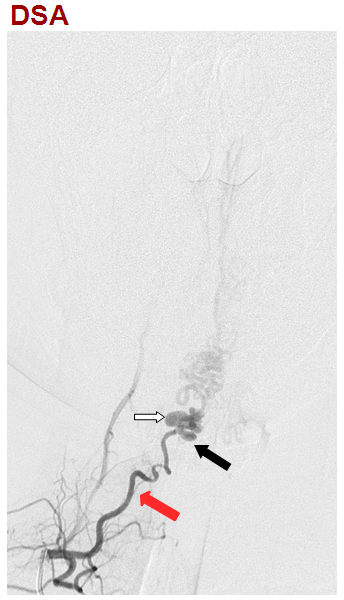

右斜位,右侧甲状颈干造影动脉期,显示颈升动脉(红箭)供应颈4-5水平瘘口(黑箭),静脉迅速出现,伴静脉球形成(白箭)。